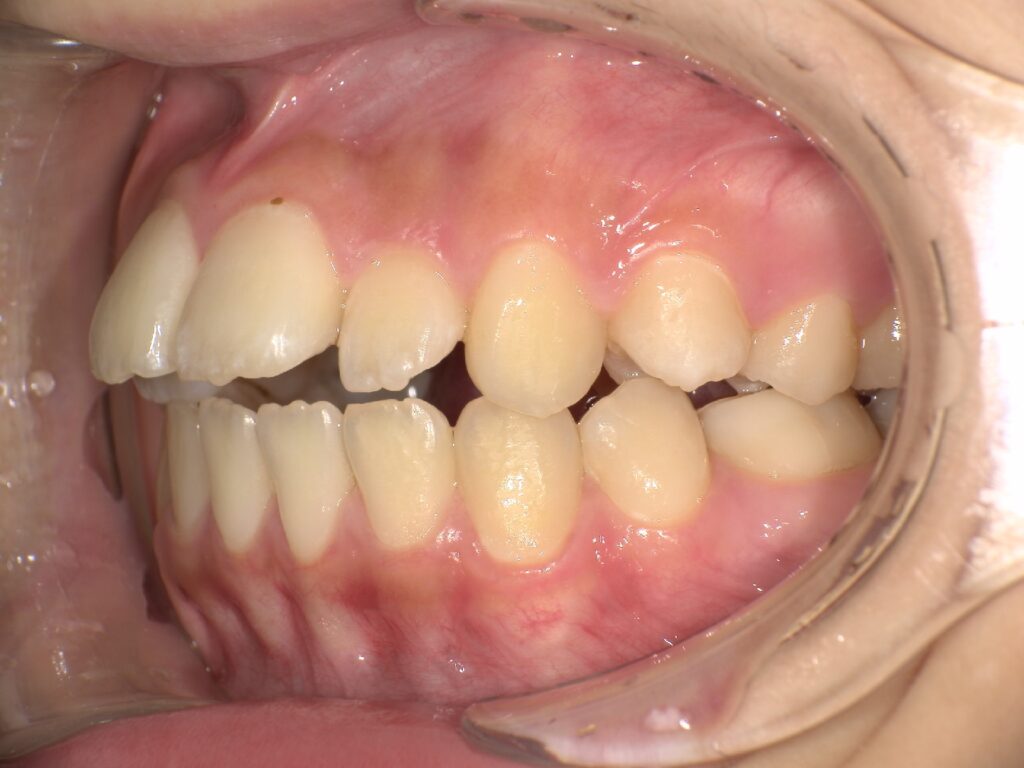

上顎の前歯が大きく突出しています

明らかに前歯の突出感が改善し、患者様はこの時点でとても喜ばれていました

矯正治療終了時 部分矯正ということもあり、短期間で矯正治療を終了することができました